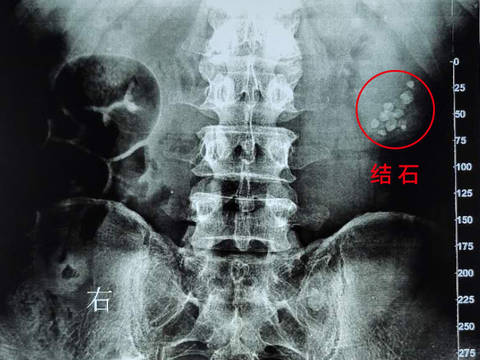

巨大结石无症状?微创手术解难题